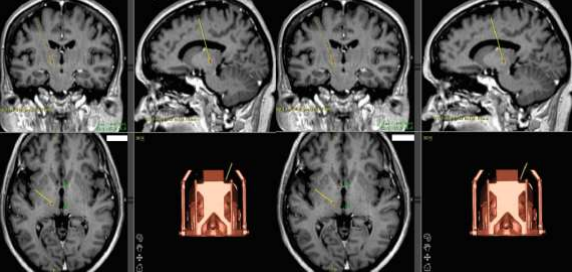

Surgical procedures were conducted using the CRW Stereotactic system, facilitated by planning stations from Radionics (StereoPlan, Atlas) and Medtronic (FrameLink) software (6,7). The Vim target was identified using an indirect method based on AC and PC landmarks. The STN and GPi targets were identified through direct targeting of T2, inversion recovery, and proton density-weighted images (Table 1).

Figure I: Calculated target coordinates for RF destruction. A -ventro- lateral intermediate thalamic nucleus (Vim). B - globus pallidus pars interna (GPi)

Intraoperative macrostimulation was used to precisely determine the optimal target location in all cases. For Vim and GPi lesioning, a radiofrequency (RF) electrode was employed with an exposed tip diameter of 2.1 mm and tip length of 2.0 mm. For STN lesioning, an RF electrode with a tip diameter of 1.4 mm and tip length of 3.0 mm was used.